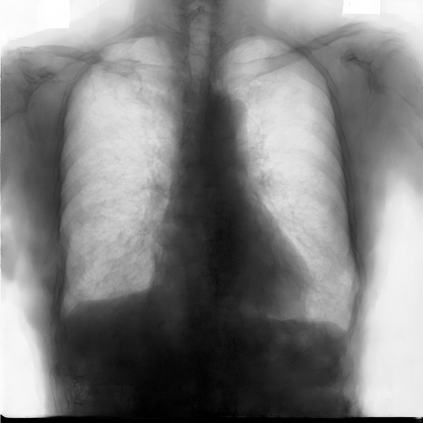

Multi-organ segmentation of X-ray images is of fundamental importance for computer aided diagnosis systems. However, the most advanced semantic segmentation methods rely on deep learning and require a huge amount of labeled images, which are rarely available due to both the high cost of human resources and the time required for labeling. In this paper, we present a novel multi-stage generation algorithm based on Generative Adversarial Networks (GANs) that can produce synthetic images along with their semantic labels and can be used for data augmentation. The main feature of the method is that, unlike other approaches, generation occurs in several stages, which simplifies the procedure and allows it to be used on very small datasets. The method has been evaluated on the segmentation of chest radiographic images, showing promising results. The multistage approach achieves state-of-the-art and, when very few images are used to train the GANs, outperforms the corresponding single-stage approach.